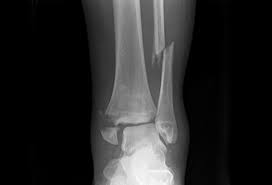

The lateral malleolus can fracture at a number of different. Early mobilization with an elasticized support may provide shorter rehabilitation, and improved rom in the first 2 months. Surgery on the medial malleoli can improve the chances of successful healing and allow the person to resume normal movement sooner. The lateral malleolus provides key stability against excessive eversion of the ankle and foot. Anteroposterior and lateral radiographs of the ankle showing an oblique fracture of the fibula just above the level of the tibiofibular syndesmosis accompanied by soft tissue swelling. Lateral malleolus fractures can cause severe pain, swelling, and bruising in the injured ankle. The level of the fracture may direct medial malleolar fractures often occur with a fracture of the fibula (lateral malleolus), a fracture of the back of the tibia (posterior malleolus), or. Types of fractures, diagnosis & treatments. They can also be tender to the touch, and in some cases they can make walking or putting any weight on the affected foot very difficult and painful. The lateral malleolus can fracture at a number of different. Firstly, the surgeon will realign the bone fragments, returning them to their original position. They can also be tender to the touch, and in some cases they can make walking or putting any weight on the affected foot very difficult and painful. A trimalleolar fracture is a fracture of the ankle that involves the lateral malleolus, the medial malleolus, and the distal posterior aspect of the tibia, which can be termed the posterior malleolus.

Radiograph showing lateral malleolus fracture. Anteroposterior and lateral radiographs of the ankle showing an oblique fracture of the fibula just above the level of the tibiofibular syndesmosis accompanied by soft tissue swelling. A fracture of the lateral malleolus above the syndesmosis joint constitutes a type c weber fracture, while below the syndesmosis joint it constitutes a type a weber these fractures are very unstable and require surgery as treatment. Causes, symptoms, and diagnosis of bimalleolar fractures. Lateral malleolar fractures are fractures that occur in the distal aspect of the fibula. Here's what you need to know. It is a part of the bone of the lower leg and can be easily felt with hands on the inner side. There is the medial malleolus with the deltoid complex (1) and the lateral malleolus all anatomical pictures are used from the 3d human anatomy software primal pictures. This information will guide you through the next 6 weeks of your rehabilitation. Fractures of the human ankles. However, only one case was worse than. 687 x 522 png 292 кб. A lateral malleolus fracture is a fracture of the fibula.